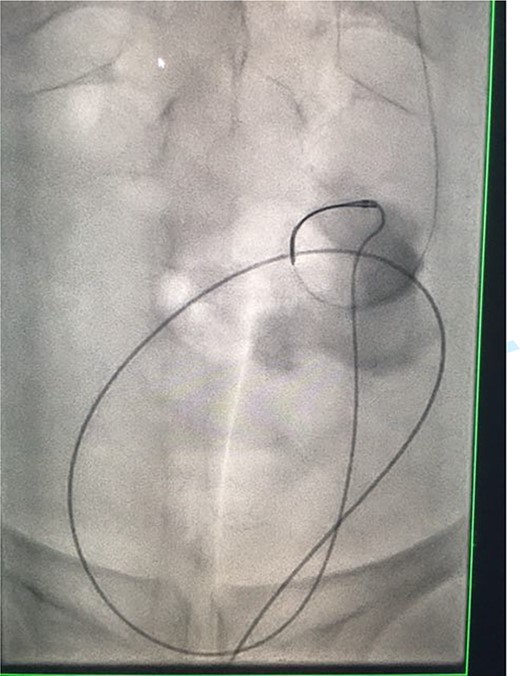

Under conscious sedation, using the previously inserted right percutaneous nephrostomy, antegrade access was achieved into the intrarenal collecting system and then into the proximal ureter. An 8 Fr × 11-cm access sheath was introduced. A guidewire was advanced antegradely through the site of ureteric transection and coiled in a position adjacent to the position of the guidewire that had been inserted retrogradely. A Gooseneck snare catheter was then passed over the guidewire and the snare was inserted (Figs 4 and 5). Under fluoroscopic guidance, the retrograde wire was retrieved and brought externally via the nephrostomy site, achieving through-and-through wire access (Figs 6 and 7).

Fluoroscopic images showing the retrograde wire successfully retrieved and brought externally via the nephrostomy site, achieving through-and-through wire access.